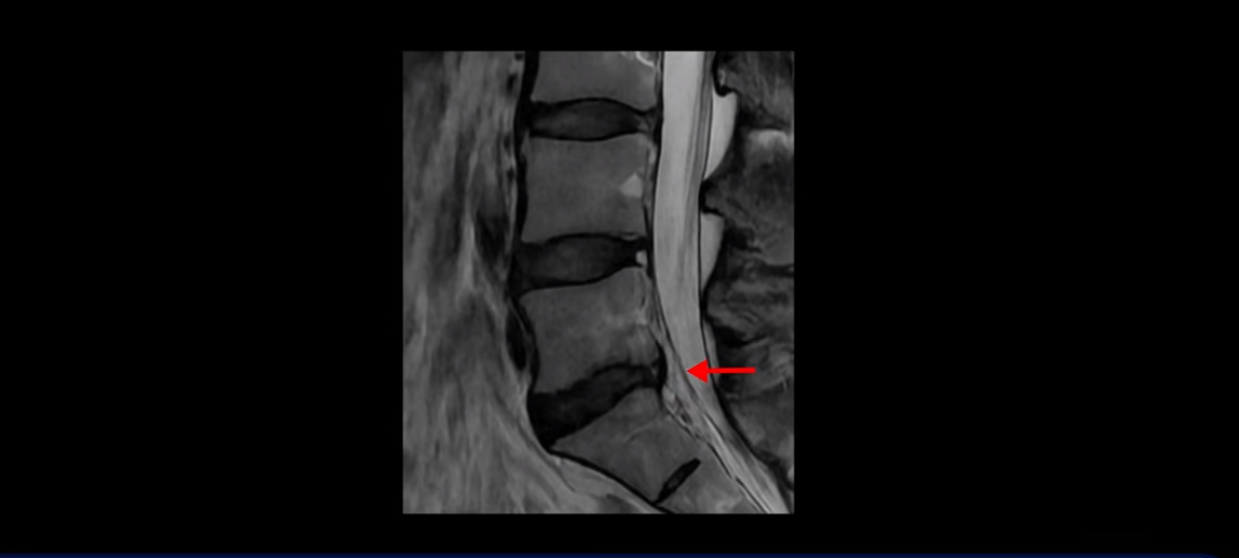

우선 이분 허리 MRI를 보면 5번 1번에 퇴행성 디스크가 있지만 방사통을 일으킬 만큼 신경을 누르고 있어 보이지 않습니다.

오른쪽으로 디스크가 약간 찢어져 보이는데, 작년에 찍은 MRI에서도 보이는 것이라 오래 전에 찢어진 후 아문 흔적으로 보입니다.

중요한 것은 오른쪽 다리에 심한 방사통이 있다든가 재채기를 못 한다거나 허리를 구부리거나 몸을 살짝 비틀 때 날카로운 통증이 없습니다. 즉, 섬유륜이 최근에 찢어진 게 아닌 겁니다.

4번 5번과 3번 4번 마디도 디스크가 중앙으로 살짝 밀려나와있지만 최근에 섬유륜이 찢어진 것도 아니고, 신경 다발을 누를 정도로 심하게 밀려나와 있는 것도 전혀 아닙니다.

양쪽 신경 가지가 빠져나가는 추간공도 충분히 넓어서 신경학적 방사통을 일으킬 여지가 없습니다.

그럼 이 환자분의 양쪽 다리 저림과 발 저림 그리고 앉기만 하면 5분 내로 심한 허리 통증, 엉덩이 통증이 발생하는 원인은 뭘까요? 저희가 이런 디스크 내장증 얘기를 들으신 환자분들 치료 후기에서 수없이 설명하지만, 이런 증상이 디스크가 원인이 아닙니다. 이분도 여러 병원에서 증상과 MRI가 일치하지 않는다고 들으셨는데요.